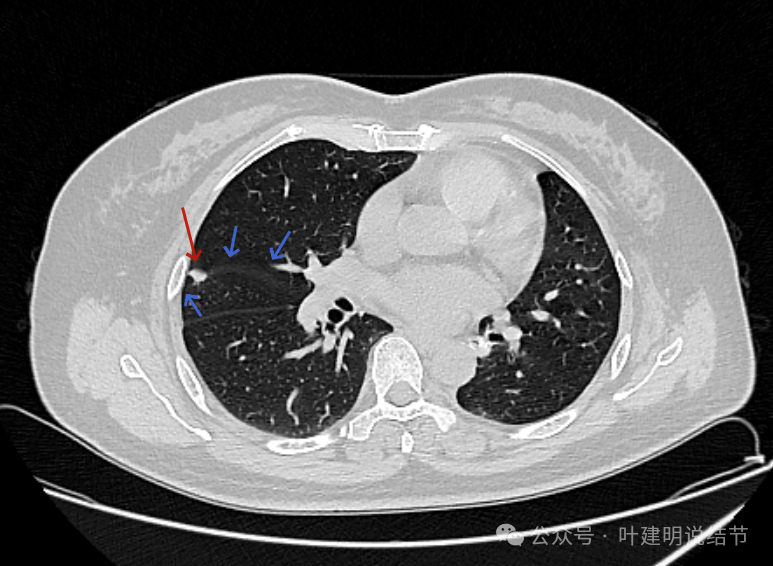

2022年8月术前左下病灶的样子,是混合磨玻璃密度,边缘毛糙,灶内有细支气管扩张,近侧有支气管截断似的,胸膜有牵拉,整体轮廓清,瘤肺边界也较清,是典型浸润性腺癌的影像表现。

2023年2月时右上叶同一处没有明显病灶。

右上前后相差15个月的对比。